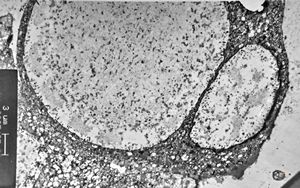

M,27y. | sea-blue histiocyte syndrome